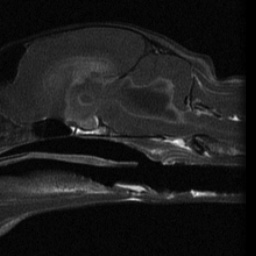

Today’s case is a 9-month-old male neutered domestic short haired cat with lethargy, inappetence, and generalized ataxia and weakness.

Axial and sagittal images through the brain were obtained in T1 and T2 weighted and FLAIR sequences. The ventricular system is markedly dilated. On FLAIR sequences, the CSF is abnormally hyperintense. Extending from the lining of the lateral ventricles, are bilaterally symmetric lobular structures that are isointense to brain on both T1 and T2 sequences and are suspected to be enlarged choroid plexes.The lining of the ventricular system is thickened and markedly contrast enhancing. The lobular structure suspected to be choroid plexes are also contrast enhancing.

Impressions: Severe ependymitis and hydrocephalus.

• Feline Infectious Peritonitis (FIP)

The CSF in the ventricles had a high cell count as well as high protein content. This caused it not to suppress during the FLAIR sequance, giving a clue to the underlying abnormality. The hydrocephalus and enlarged choroid plexus were likely secondary to inflammatory infiltrate and debris impeding drainage.